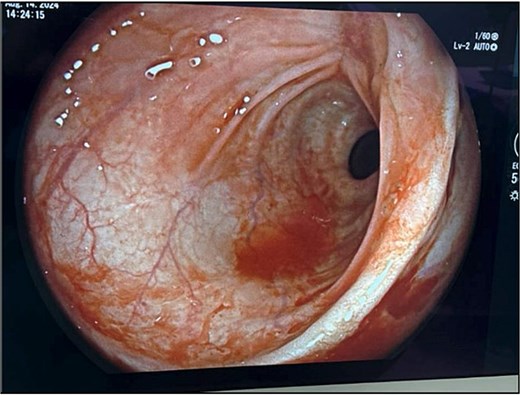

Examination under anesthesia with flexible sigmoidoscopy revealed a right lateral rectal wall disruption approximately 8 cm from the anal verge, involving close to 30% of the rectal circumference (Fig. 2). In the absence of peritonitis, the patient was admitted for observation and managed nonoperatively with bowel rest and intravenous ceftriaxone 1 g every 24 h, and metronidazole 500 mg every 12 h.

Initial findings on exam under anesthesia with flexible sigmoidoscopy revealing right lateral rectal wall disruption 8 cm from the anal verge, involving ~30% of the luminal circumference.